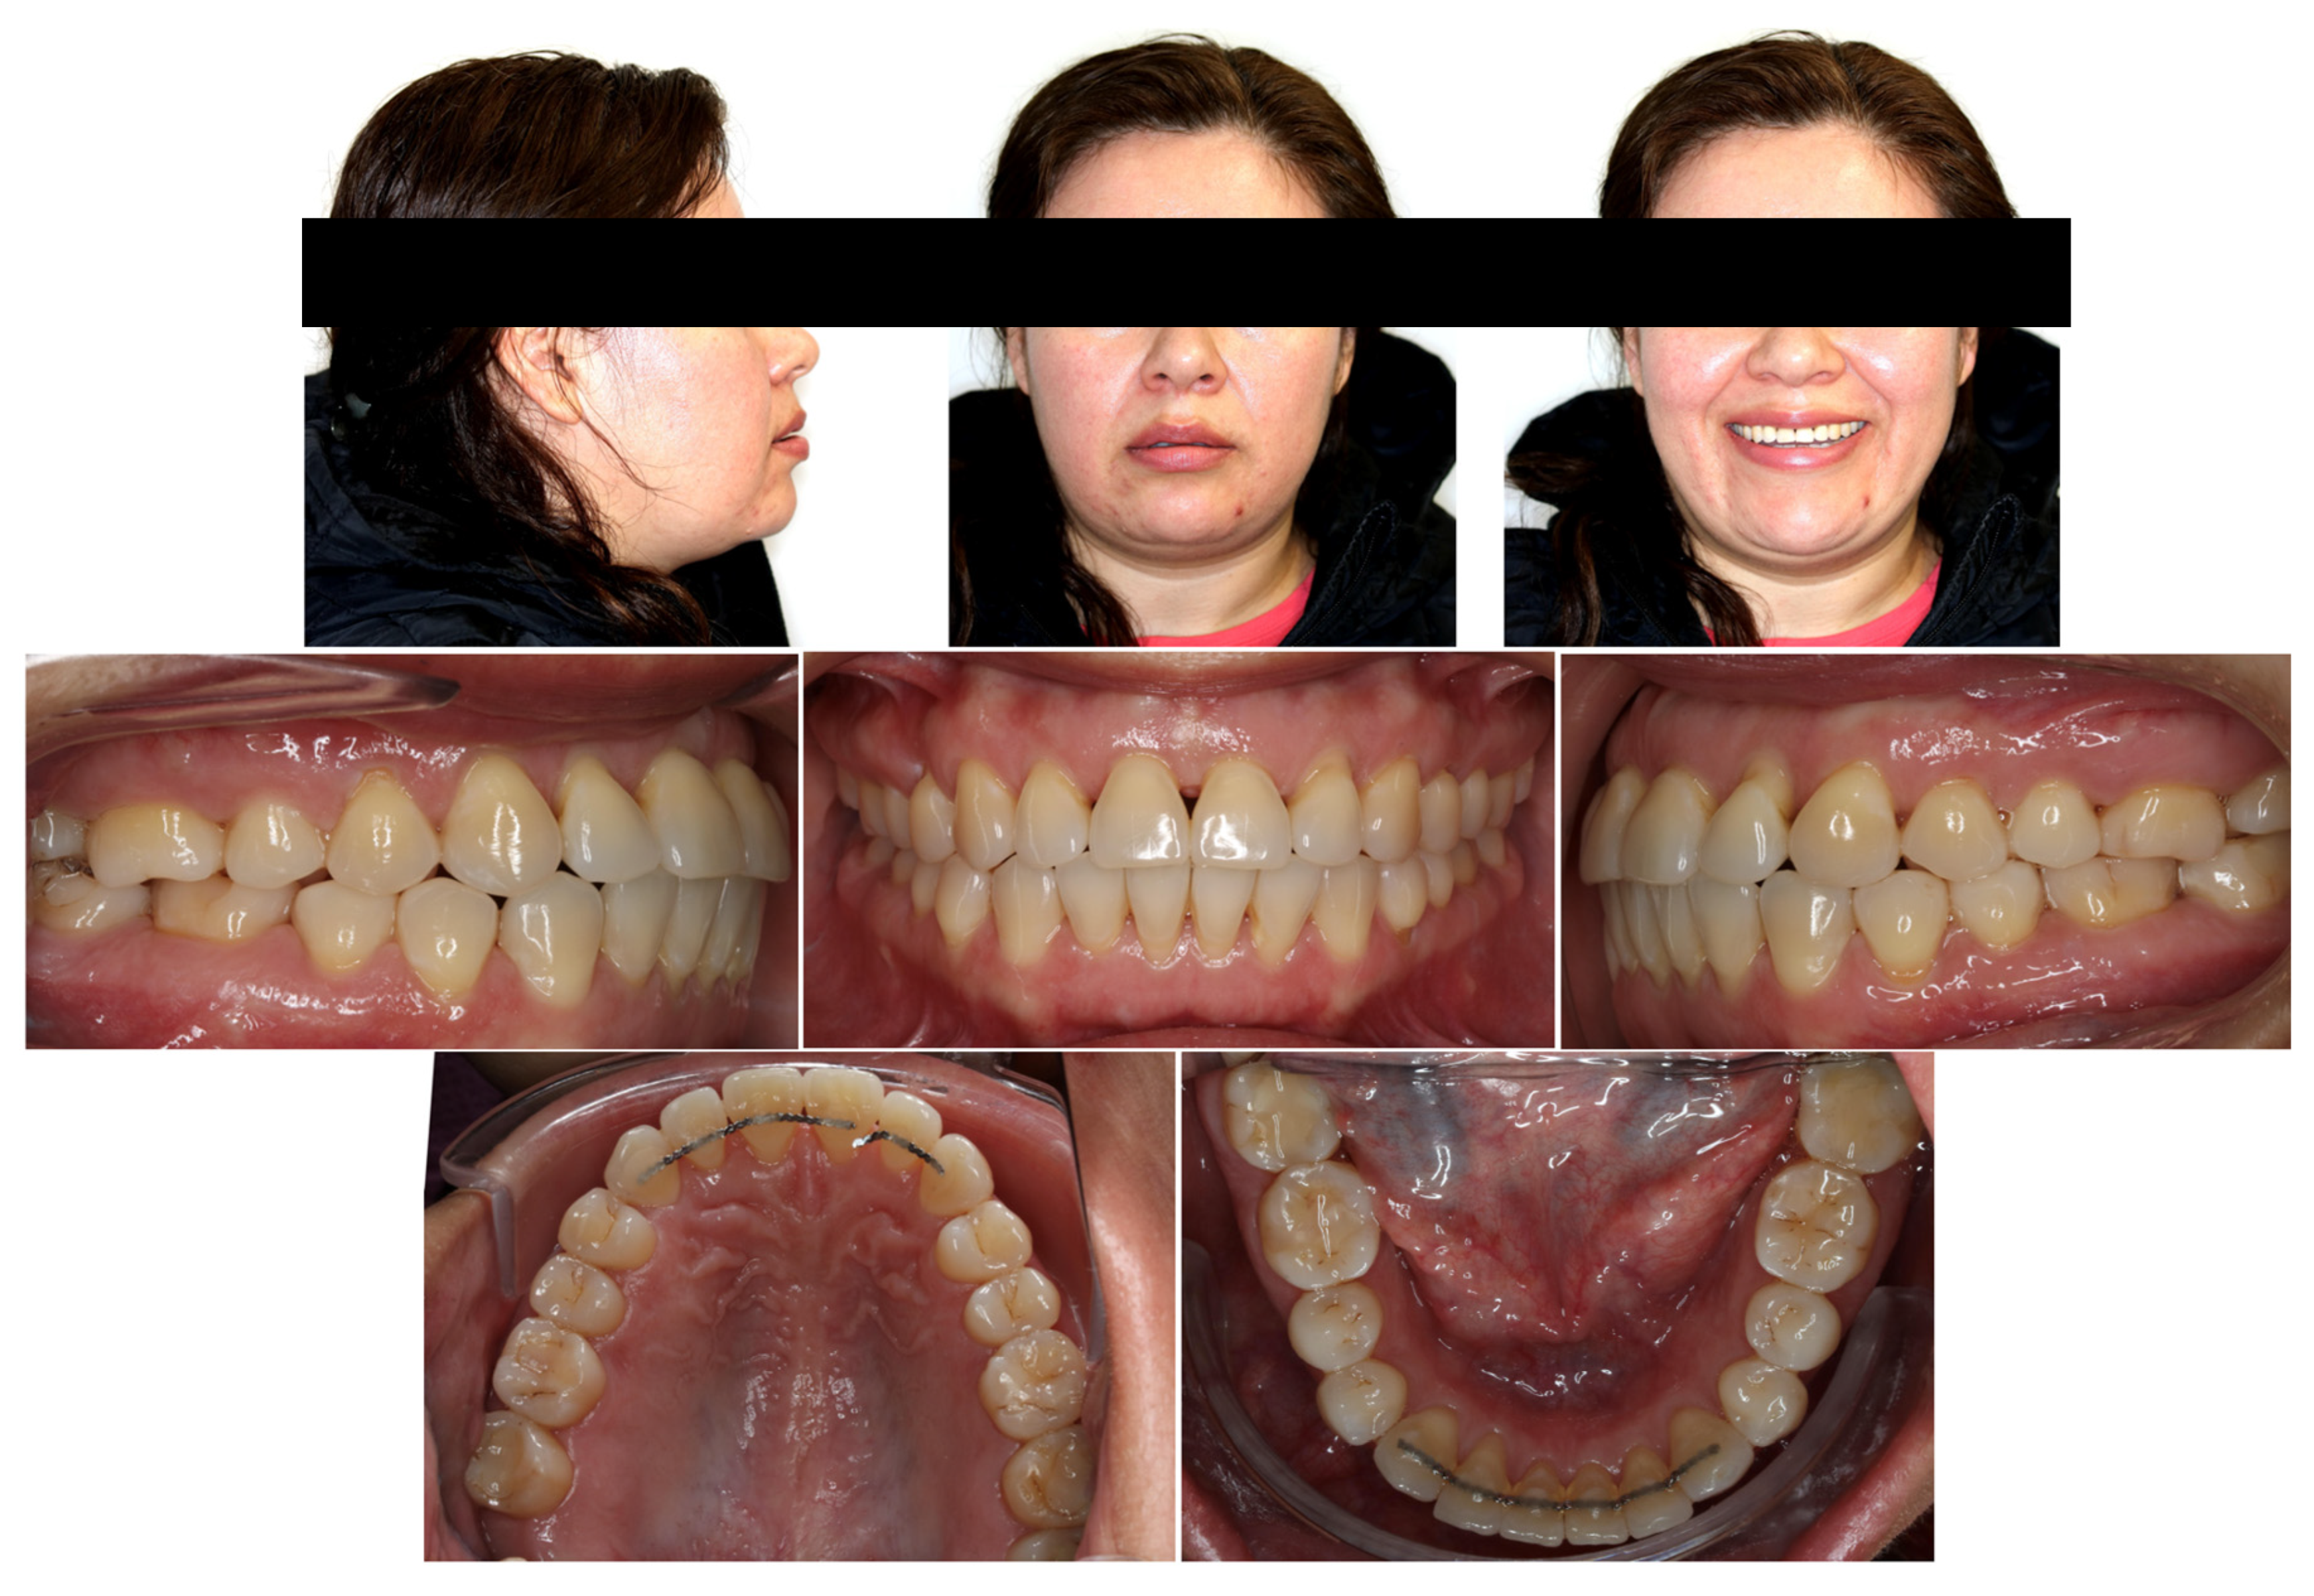

The patient’s chief complaint was addressed, and the patient-centered treatment objectives were achieved, with good esthetic and occlusal outcomes. The post-treatment result shows improvement in lip closure, smile esthetics and overbite (Figure 5). The tongue thrust habit was addressed, and the patient has become genuinely aware of its importance from a stability perspective. Along with the tipping of the occlusal planes, a normal overbite was achieved through a combination of maxillary posterior teeth intrusion, maxillary and mandibular incisors’ relative extrusion, i.e., retroclination and retraction, and mandibular autorotation (Figure 6 and Table 1). Such outcomes were accomplished via the application of miniscrew-assisted sectional mechanics, IPR and inter-arch elastics. The post-treatment panoramic and periapical radiographs showed good root parallelism, without significant root shortening, worsening of the root/crown ratio at the maxillary incisors or development of other pathologies (Figure 7). Follow-up records after 56 months demonstrated a stable occlusion with increased incisal display and an overbite (Figure 8 and Figure 9).

Figure 5.

Post-treatment facial and intraoral photographs.

Figure 8.

Facial and intraoral photographs taken 56 months after debonding.

It is important to consider the 3-D changes associated with intrusion of the maxillary posterior teeth. In the vertical dimension, a combination of intrusion of the maxillary posterior teeth and relative extrusion of the maxillary anterior teeth provided correction of the patient’s AOB with an improved incisal display and smile arc (Figure 5). Although she could have benefited from more incisor extrusion, such “true” extrusion would have deteriorated her periodontal status. Furthermore, it might have worsened her smile esthetics given the presence of notable black triangles (Figure 8). According to Scheffler and colleagues (2014), 2.3 mm of maxillary molar intrusion improves an overbite by 2.2 mm as opposed to the conventionally assumed 4 mm, possibly because of mandibular molar extrusion [14]. In the present case, mandibular molars were maintained, maxillary molars were intruded ~2 mm, maxillary incisors were “relatively” extruded ~3 mm, and mandibular incisors were slightly extruded. The overall change in overbite was about 5.1 mm, from an initial open bite of −3.9 mm to a final overbite of 1.2 mm.